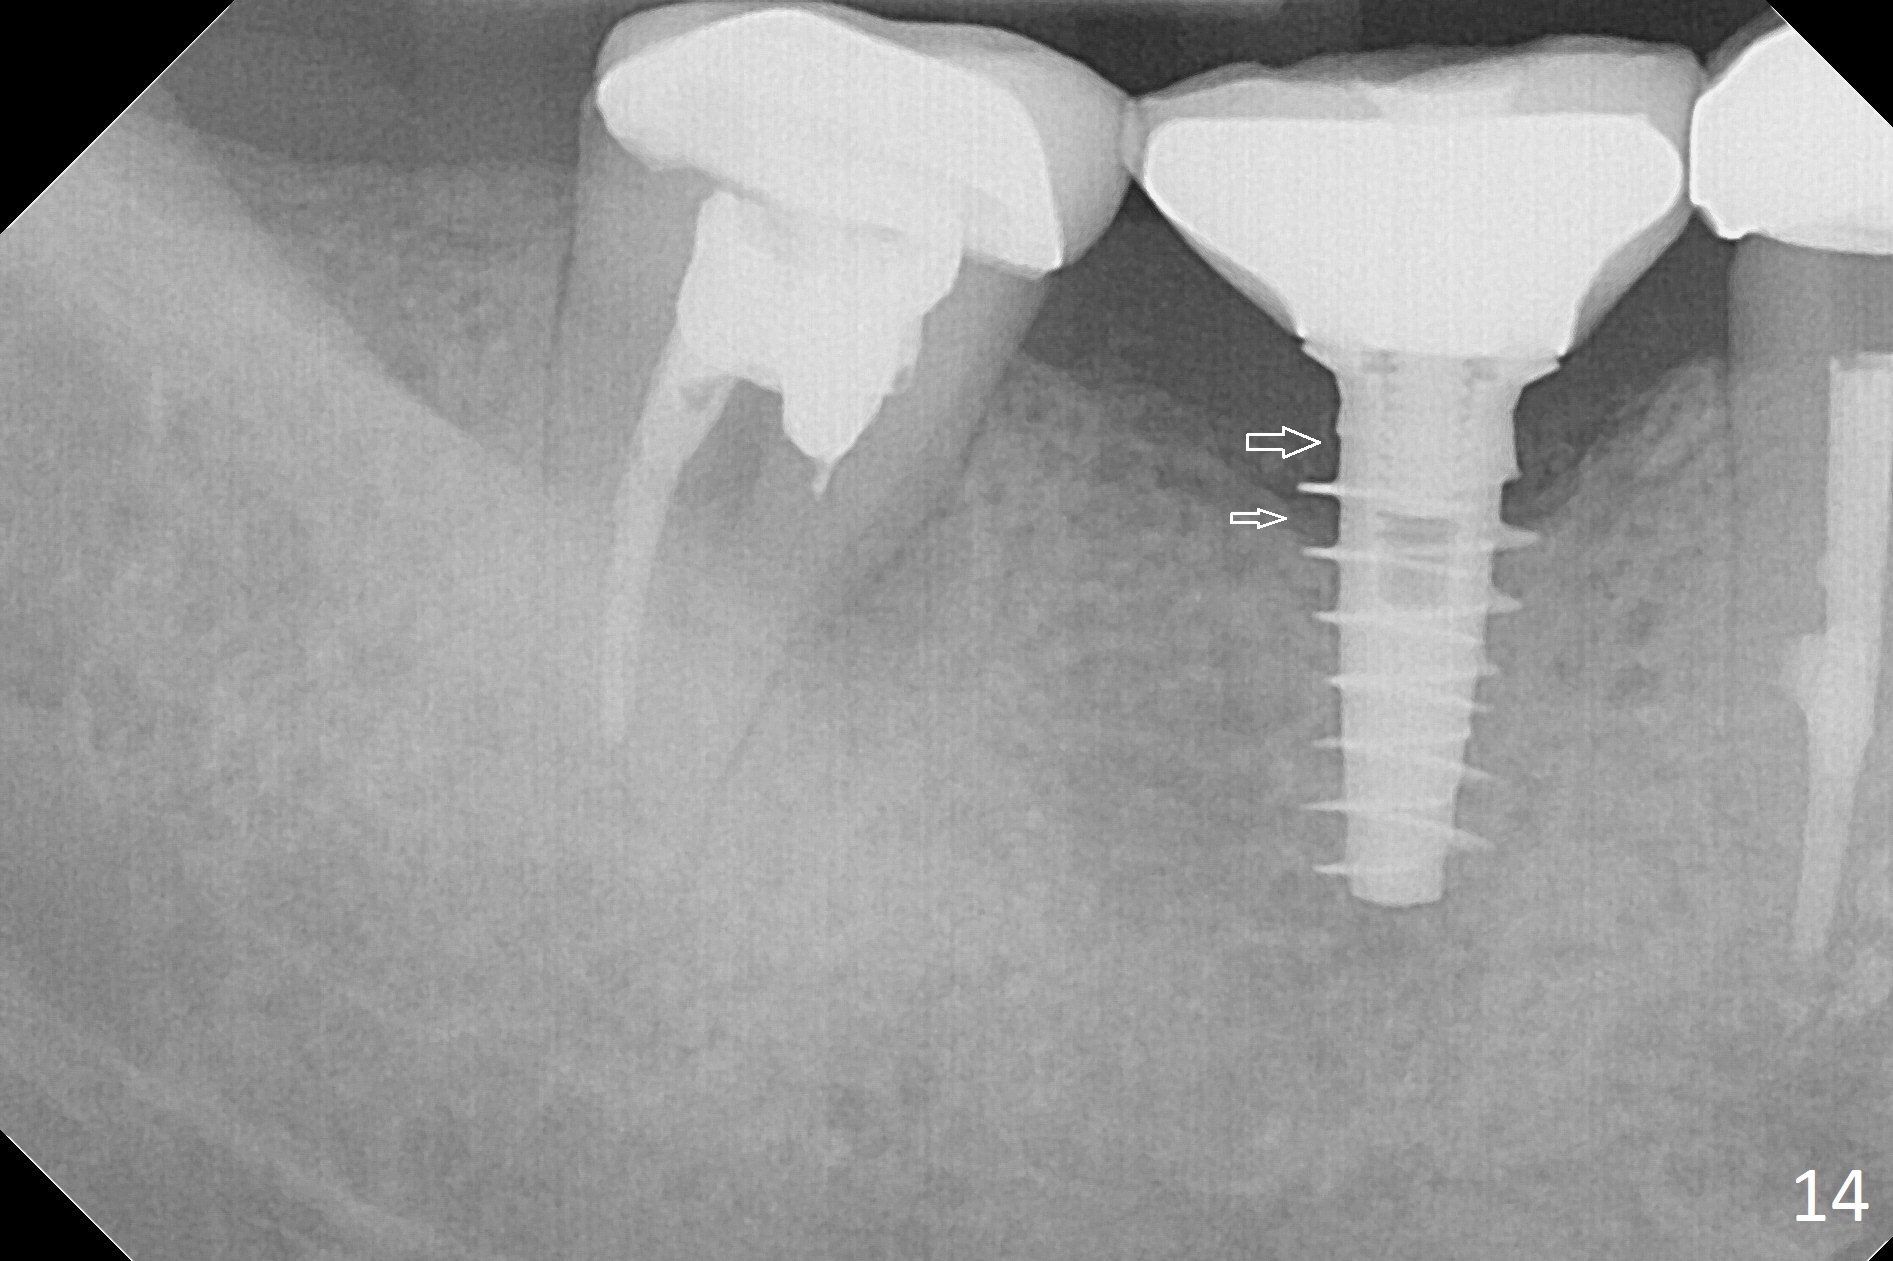

Splinted provisional is fabricated #30 and 31 one month postop. The patient returns for final restoration (single units) nearly 4 months postop (Fig.11). Since the margin is subgingival, a screw type crown is fabricated for #30 (Fig.12). The buccal gingiva looks convex after healing cap removal (Fig.13, as compared to Fig.4 (concave)). PA is taken immediately post tightening and cementation (Fig.14, 5 months postop). It appears that new bone has grown between the most coronal threads (arrows). The bone density immediately around the implant appears to increase 1.5 years post cementation (Fig.15,16). She returns because of failure of 18-20 bridge (implants will be placed at 18/19). The implant at #30 is in fact not placed deep enough; the coronal threads seem to be exposed, although there is no periimplantitis (Fig.17 CT). The tooth #31 is symptomatic; the mesial canal is missing (Fig.18 M, <). The gingiva around the crowns at #30 and 31 remains healthy 2 years 4 months post cementation (Fig.19). Metal exposure of the crown at #31 is intentional. Occlusal reduction is done to alleviate periapical re-infection (Fig.18).